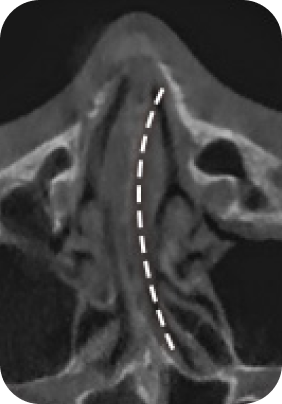

맘모톰, 비후성/알레르기 비염, 비중격 만곡증, 비밸브 협착증 등

질환에 따라 3DCT, 내시경 검사, 고해상도 초음파를 통해 정밀진단 후

정확한 증상에 따라 보험 실비 청구가 가능합니다.

대학병원급 검사 장비

디에이성형외과에서는 대학병원급 검사 장비 시스템

각 분과의 전문의와 성형외과 전문의가 협진하여